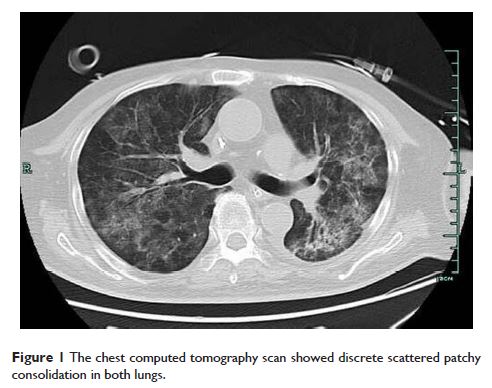

Case Report

- 作者:Mei-fang Yang, Hai-nv Gao, Lan-juan Li

- 期刊:Therapeutics and Clinical Risk Management